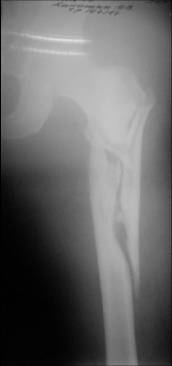

Re: Severely comminuted Trochenteric #

I would use a small wire distractor mentioned in the list some times. Proximal wire is in the iliac crest in AP direction. The leg is adducted. I attached some images. At the AP view under image intensifier you can see adduction but even slight valgus reduction.